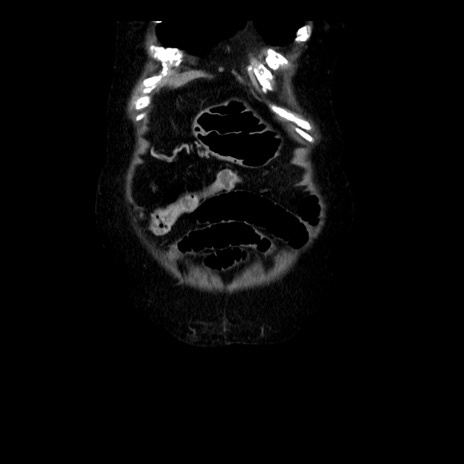

横断像

【症例】 90歳代女性

【主訴】 腹痛・嘔吐

【現病歴】今朝から左側腹部痛を認めた。 経過観察していたが、嘔吐を認めたため来院。

【既往歴】 子宮癌術後

【身体所見】 意識清明、BP 127/54mmHg、P 98bpm Sp02 95%(RA)、BT 35.8°C、腹部平坦・軟腸ぜん動音聴取良好、右下腹部圧痛(+) 反跳痛なし

【データ】WBC 9800、CRP 0.46